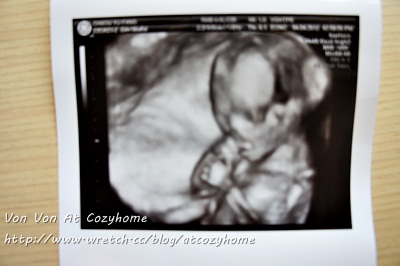

4/4(周三) 今天醫生幫我預約了高層次超音波,這是我住院以來最期待最開心的一天,因為可以清楚地看見肚腹裡的妹妹。柔和的音樂流淌在檢驗室裡,我安安靜靜地躺在那裏,KJ陪在我身邊一起看著妹妹一下吃手、一下翻身、一下揮手的影像,雖然是第二胎了,還是充滿期待迎接這個寶寶,我們都好愛她,她是上帝的產業,上帝的恩典。

懷孕約20周,妹妹的高層次超音波照,很健康很秀氣..只是有點骨感。4/5(周四) 我輕聲朗讀著「God’s creative power for healing」,持續禱告,體力已漸恢復。